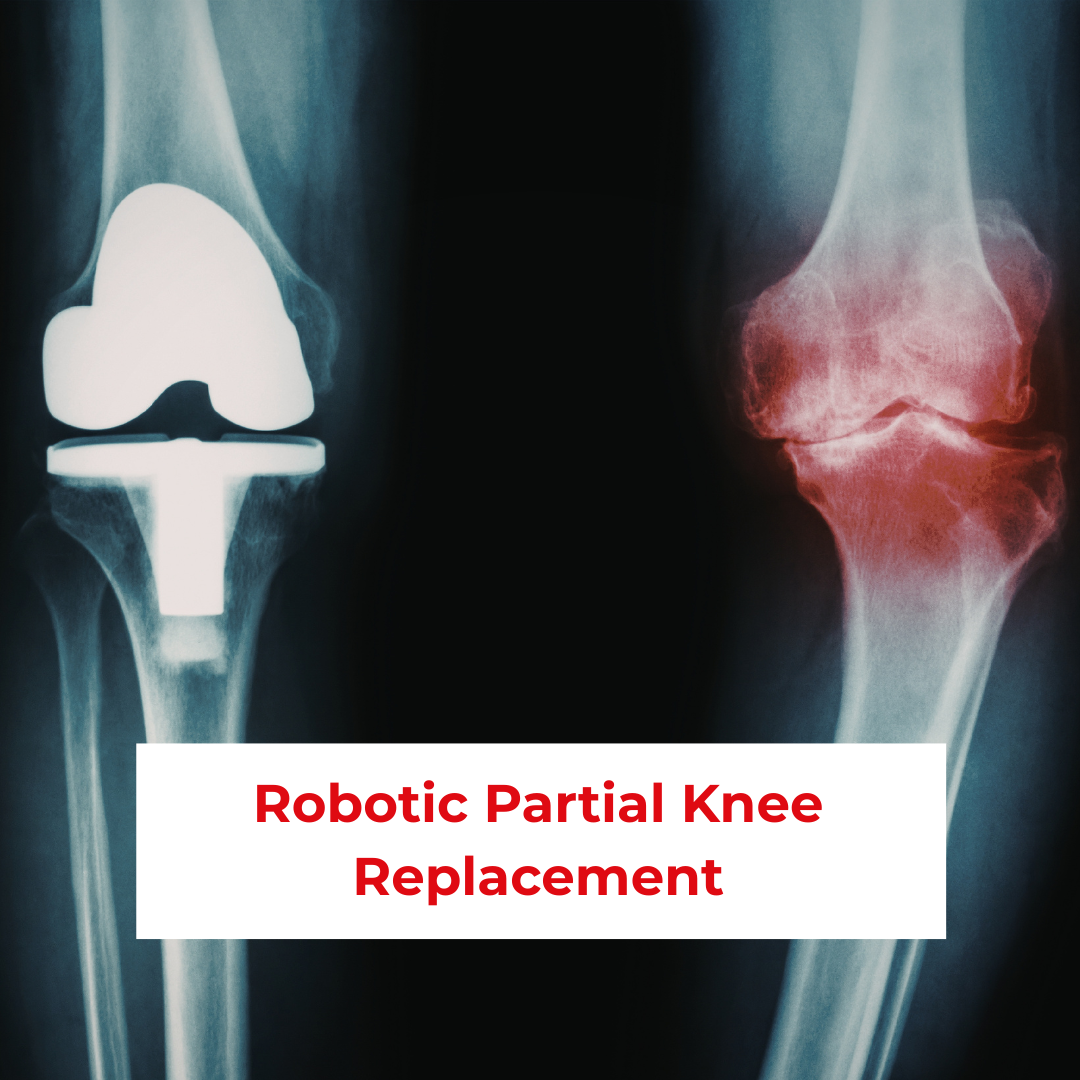

Knee pain caused by localized joint damage can significantly affect mobility and daily activities. In many patients, arthritis or joint degeneration affects only one compartment of the knee rather than the entire joint. In such cases, partial knee replacement is an effective alternative to total knee replacement. With advancements in medical technology, robotic-assisted partial knee replacement has enhanced surgical precision, improved recovery, and preserved natural knee movement. For patients seeking advanced joint preservation surgery, Ruban Memorial Hospital is a trusted center for Robotic Partial Knee Replacement in Patna, Bihar.

Robotic partial knee replacement is an advanced orthopedic procedure designed to replace only the damaged portion of the knee joint while preserving healthy bone, cartilage, and ligaments. Using robotic-assisted technology, surgeons can plan and perform the procedure with exceptional accuracy based on the patient’s unique knee anatomy.

Unlike total knee replacement, partial knee replacement maintains more of the natural knee structure, resulting in better joint function and faster recovery.